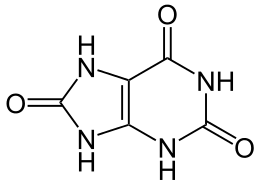

Gout (/ɡaʊt/ GOWT[9]) is a form of inflammatory arthritis characterized by recurrent attacks of a red, tender, hot and swollen joint,[4][10] caused by the deposition of needle-like crystals of uric acid known as monosodium urate crystals.[11] Pain typically comes on rapidly, reaching maximal intensity in less than 12 hours.[7] The joint at the base of the big toe is affected (Podagra) in about half of cases.[12][13] It may also result in tophi, kidney stones, or kidney damage.[3]

Gout is due to persistently elevated levels of uric acid (urate) in the blood (hyperuricemia).[4][7] This occurs from a combination of diet, other health problems, and genetic factors.[3][4] At high levels, uric acid crystallizes and the crystals deposit in joints, tendons, and surrounding tissues, resulting in an attack of gout.[3] Gout occurs more commonly in those who regularly drink beer or sugar-sweetened beverages; eat foods that are high in purines such as liver, shellfish, or anchovies; or are overweight.[3][5] Diagnosis of gout may be confirmed by the presence of crystals in the joint fluid or in a deposit outside the joint.[3] Blood uric acid levels may be normal during an attack.[3]

Gout is a disorder of purine metabolism,[7] and occurs when its final metabolite, uric acid, crystallizes in the form of monosodium urate, precipitating and forming deposits (tophi) in joints, on tendons, and in the surrounding tissues.[19] Microscopic tophi may be walled off by a ring of proteins, which blocks interaction of the crystals with cells and therefore avoids inflammation.[43] Naked crystals may break out of walled-off tophi due to minor physical damage to the joint, medical or surgical stress, or rapid changes in uric acid levels.[43] When they break through the tophi, they trigger a local immune-mediated inflammatory reaction in macrophages, which is initiated by the NLRP3 inflammasome protein complex.[3][19][43] Activation of the NLRP3 inflammasome recruits the enzyme caspase 1, which converts pro-interleukin 1β into active interleukin 1β, one of the key proteins in the inflammatory cascade.[3] An evolutionary loss of urate oxidase (uricase), which breaks down uric acid, in humans and higher primates has made this condition common.[7]